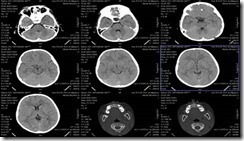

Gambar 24, Radiograf An O: Potongan Axial

Gambar 25, Radiograf An O: Potongan Coronal

Gambar 26, Radiograf An O: Potongan Sagital

Setelah dilakukan pemeriksaan CT-Scan Kepala dengan klinis Corpus alienum pada pasien An. O yang dilakukan dengan menggunakan potongan axial,sagital dan coronal dan dengan slice interval 4 mm kemudian diinterpretasikan oleh Dr. Adi Soewarno, Sp.Rad maka hasil yang diperoleh adalah :

Tampak Corpus alienum (Carbo pensil) memasuki samping medial Bulbus Medial Sinistra. Ujung pensil sampai kesinus ethmoidalis sinistra. Sedalam 4,29 cm dari kulit Bulbulis Oculi Sinistra.

Kesan : Corpus alienum